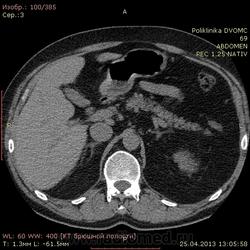

Уважаемые коллеги КТ-шники 2 часа ищу холедох, все перерыл, пересравнивал. Четко его так и не нашел, а в книжках пишут(можт обманывают?), что должен быть виден всегда. В сязи с этим огромная просьба: помогите!!!! и ткните, наконец, стрелкой в то место куда надо смотреть...спасибо.

Ткнуть, говорите? Это можно. Вспоминаем анатомию: гепатиколедох расположен в печеночно-двенадцатиперстной сваязке кпереди от воротной вены.